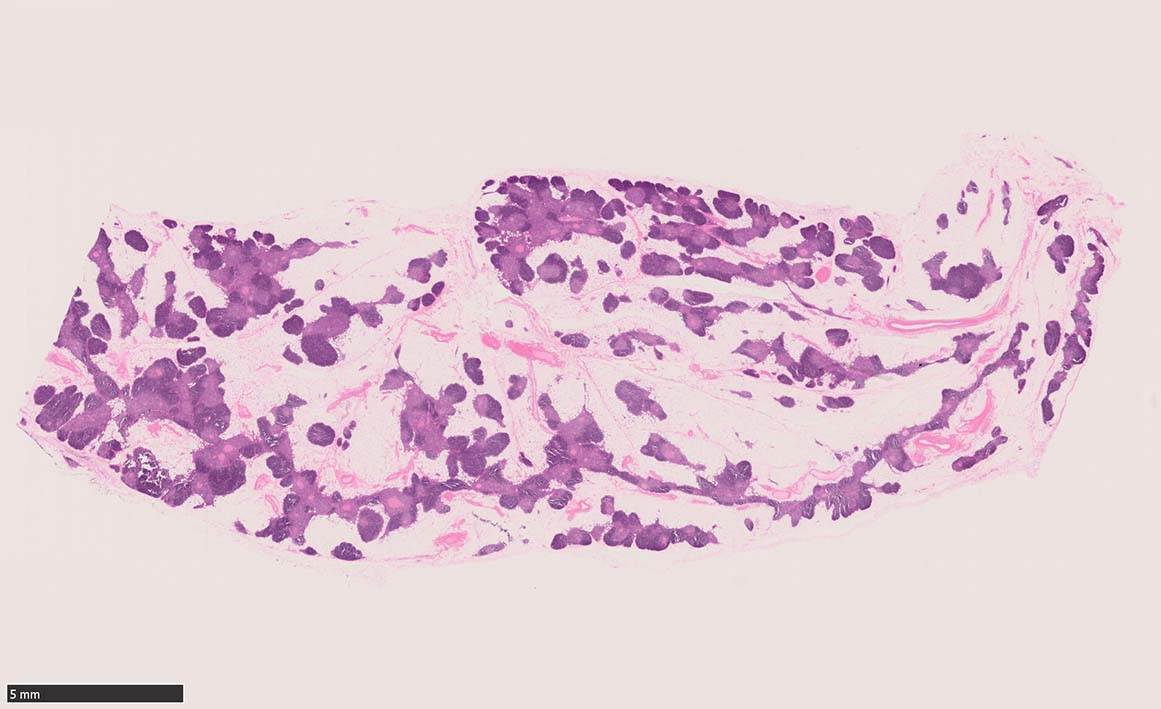

Thymus 34 year-old female

34歳女性 剖検例